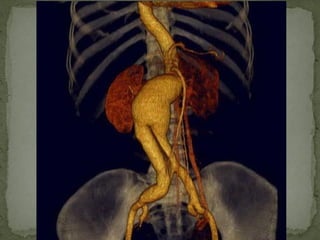

abdominal aortic

localized dilation

2 times normal's

 Infrarenal aorta

aneurysm:95 %

 Thoracic-abdominal

aneurysm : 5 %( both

thoracic and abdomianl

aorta involved )

10/20/15山血管外科网华 www.vascularcenter.cn 80

10/20/15山血管外科网华 www.vascularcenter.cn 81

10/20/15山血管外科网华 www.vascularcenter.cn 82

10/20/15山血管外科网华 www.vascularcenter.cn 84